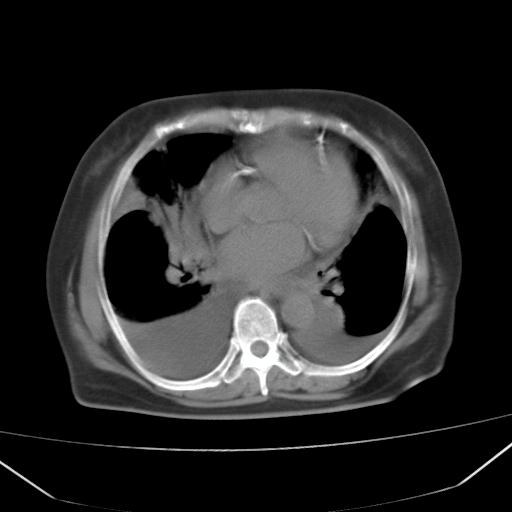

以下是引用liuyue在2008-4-19 22:25:00的发言:[br]先考虑:1.心衰伴肺水肿、双侧胸腔积液、叶间积液、双下肺不完全性肺不张; [br] 2.冠状动脉粥样硬化。

以下是引用lijuanln在2008-4-19 23:05:00的发言:[br]两侧胸腔积液,肺水肿[br]心包积液[br]提示心衰

以下是引用jiangjing在2008-4-20 10:43:00的发言:[br]结合病史支持 冠心病[冠状动脉钙化],心功能不全,肺淤血、肺水肿,双侧胸腔与斜裂积液